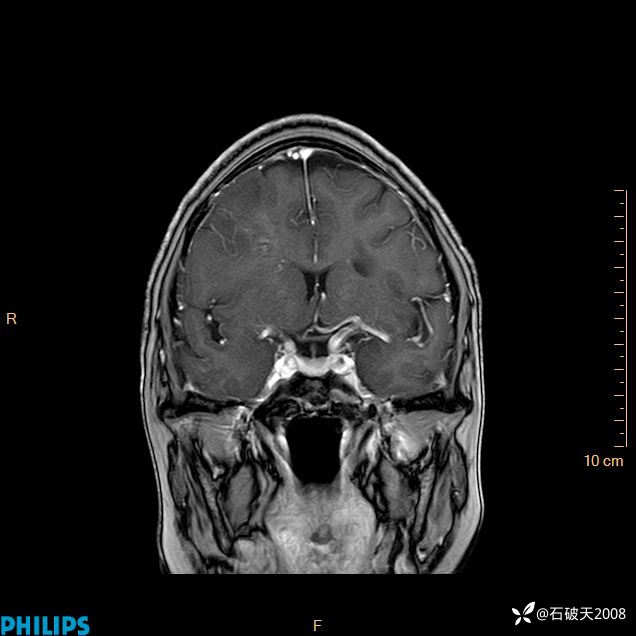

2024.2.21MR

增强冠状位